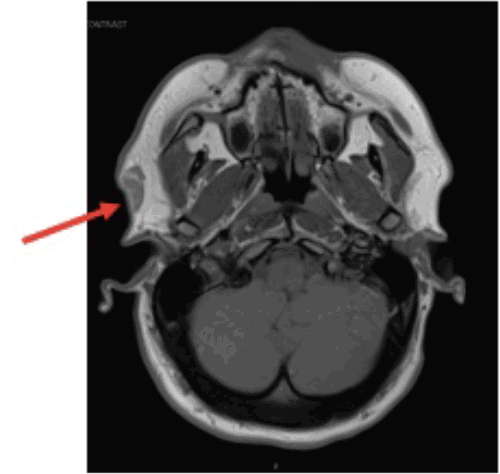

On physical examination, a 3 cm, non-tender, mobile, soft subcutaneous mass was palpated in the right preauricular region. Initial ultrasonography characterized the lesion as a hyperechoic soft tissue mass. Subsequent magnetic resonance imaging (MRI) revealed a well-circumscribed, non-specific lesion confined to the superficial soft tissues of the right preauricular area, without evidence of involvement of the underlying parotid gland or external auditory canal (Figure 1).

Figure 1. MRI of Preauricular Lipoblastoma. Published with Permission

Axial T1-weighted image demonstrating a well-circumscribed lesion (arrow) within the superficial soft tissues, appearing hyperintense to muscle